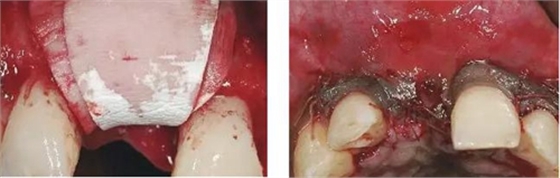

圖6、前庭溝半圓形切口,翻瓣后暴露左側和右側的骨缺損。

圖7、去除了肉芽組織和根尖感染組織,仔細沖洗后,可見雙側拔牙窩唇側骨壁有大面積缺損。

圖8、植入2顆Camlog平行壁螺紋種植體,扭矩達35Ncm。安放兩個粗直徑的愈合帽,防止軟組織退縮和凹陷。

圖9、頰側骨壁用自體骨覆蓋,Geistlich Bio-Oss®覆蓋在自體骨的外側,Geistlich Bio-Oss®同樣也要放置在基臺與牙齦之間,以支撐牙齦的外形。

圖10、為了避免對植骨區(qū)的干擾,外側覆蓋Geistlich Bio-Gide®膠原膜。